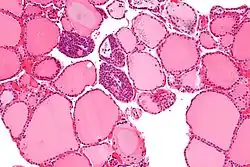

Il parenchima ha una struttura follicolare, con una serie di vescicole chiuse, i follicoli tiroidei sono formati da tireociti e sostanza colloide con intercalate le cellule parafollicolari o cellule C sia nella parete dei follicoli sia esternamente a essi.

Follicoli

I follicoli tiroidei sono delle vescicole chiuse la cui parete, l'epitelio follicolare, è formata dai tireociti o cellule follicolari, le cellule principali della tiroide atte alla produzione degli ormoni tiroidei. All'interno dei follicoli è presente del materiale amorfo, la colloide.

La forma dei follicoli dipende dallo stato funzionale della ghiandola: una tiroide in immissione in circolo di ormoni presenterà follicoli piccoli, quasi svuotati della colloide, con tireociti cilindrici (il microfollicolo)[48]; una tiroide in sintesi ormonale, invece, accumulerà molta colloide e avrà follicoli grandi con un epitelio formato da un unico strato di cellule appiattite (il macrofollicolo)[49].